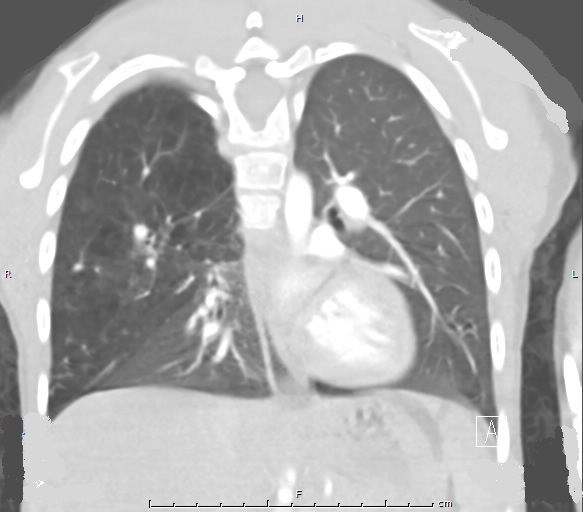

Follow-up. A CT scan of the chest was repeated approximately 1 year later and showed more cystic appearing lesions and smaller intrathoracic and abdominal masses compared to previous scans. MRI scans of the chest obtained annually during therapy demonstrated a gradual decrease in size of the hemangiomas. A follow-up CT scan of the chest performed at age 7 showed extensive centrilobular emphysema and dysplasia of most of the right lung (Figure 2). Despite the significant amount of dysplastic lung tissue, the patient did not have any recurrent illnesses or medication needs, and he remains well from a pulmonary standpoint.

Figure 2: Computed tomography of the chest with contrast performed at 7 years of age shows extensive centrilobular emphysema of the majority of the right lung.